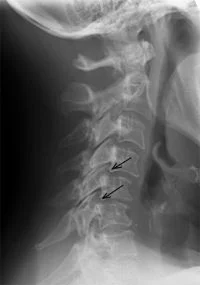

Imaging Tests

Cervical Facet joint pain dianosis

Photo- Jennifer Greene- Pinterest

Imaging methods include:

• X-rays

• MRI scans

• CT scans

However, imaging alone may not always identify the exact pain source.